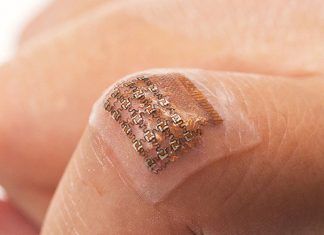

El parche que puede monitorear la presión arterial dentro de una persona

Los trabajos realizados por un grupo de investigadores de la Universidad de California, en San Diego, han conseguido sintetizar el parche capaz de monitorear de manera portátil la presión arterial central de las personas....